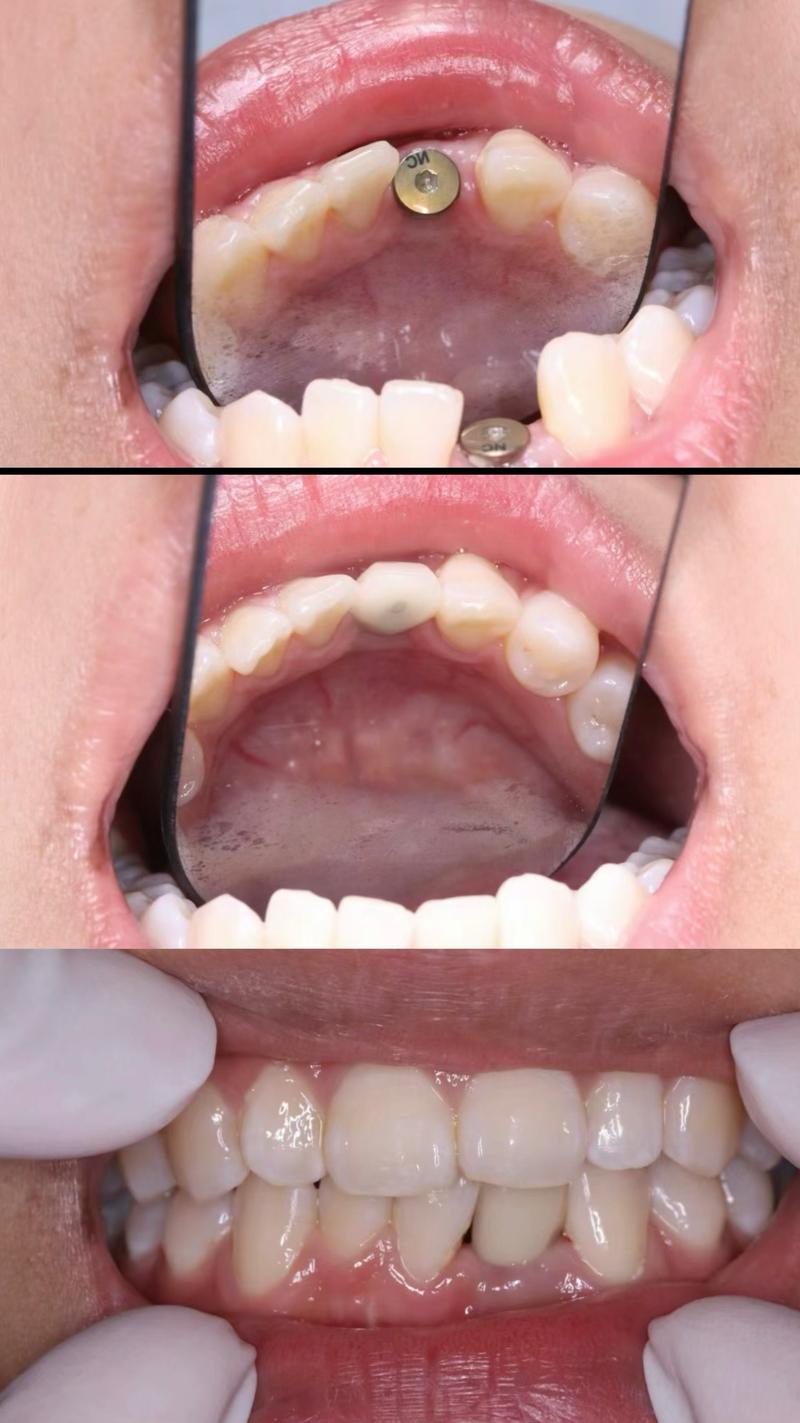

- 植入种植体:在局部麻醉下,切开牙龈,暴露牙槽骨,逐级备洞后植入种植体,缝合牙龈;

- 骨结合期:等待3-6个月,期间种植体与牙槽骨完成骨结合;

- 安装基台与牙冠:二期手术暴露种植体顶部,安装基台,取模后制作并安装牙冠,完成修复。